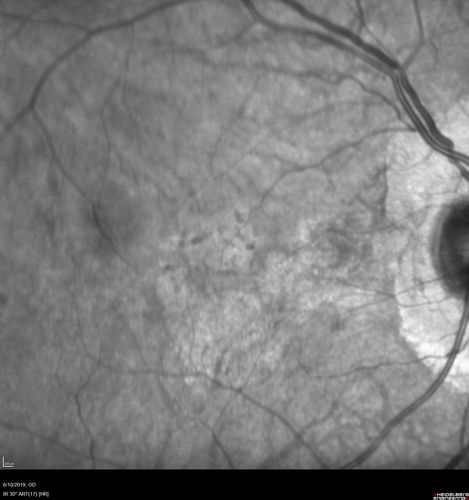

88 year old female with 2.5 mm elevated choroidal melanoma and melanosis oculi.  She also has geographic atrophy from AMD.  The right eye is the better eye with 20/40 vision.  After observation with growth, brachytherapy was done.